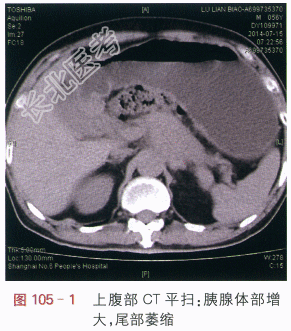

读片分析:上腹部CT平扫显示胰腺体部增大,密度均匀,尾部萎缩,胰腺周边模糊(见图105-1),增强扫描动脉期:胰腺体部不规则肿块,增强后动脉期呈低密度,肿块边缘不清,肿块包绕脾动脉、腹腔干动脉(见图105-2);门脉期:胰腺体部不规则低密度肿块,肿块包绕脾静脉(见图105-3)。延时期肿块密度呈低密度,肿块包绕腹腔血管、并向周边侵犯,左肾上腺体积增大(见图105-4)。